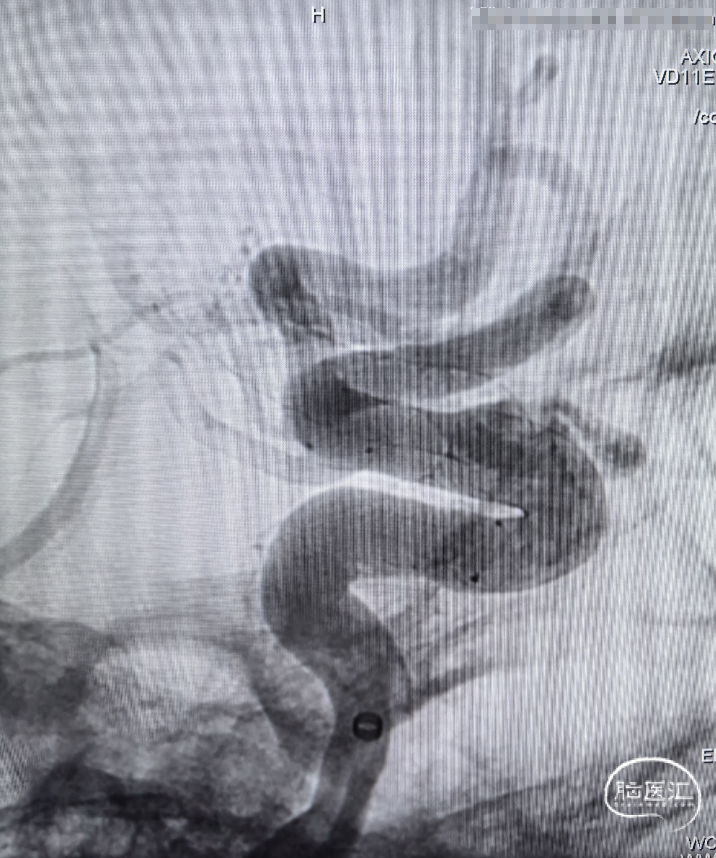

➢ 术前造影

迂曲段通桥麒麟™血流导向密网支架释放过程。